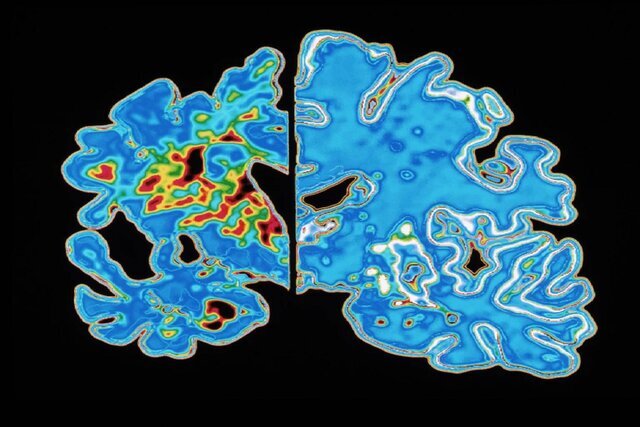

پروتئین‌های تاو غیرطبیعی می‌توانند رشته‌های درهم‌تنیده‌ای تشکیل دهند که ارتباط میان سلول‌های عصبی مغز را مختل می‌کند. آزمایش‌های تصویربرداری مغزی که این توده‌های درهم‌ تنیده تاو را شناسایی می‌کنند، گاهی در تشخیص آلزایمر استفاده می‌شوند، و مطالعات اولیه نشان می‌دهد که چنین آزمایش‌هایی شاید بتوانند زمان بروز علائم آلزایمر را نیز پیش‌بینی کنند. اما شیندلر می‌گوید این روش‌های تصویربرداری دشوار و پرهزینه هستند. در همین حال، پژوهشگران در حال بررسی آزمایش‌های ساده‌تر مبتنی بر خون هستند که می‌توانند تاو را نیز ردیابی کنند.

برای مشخص کردن «ساعت» مولکولی خود، شیندلر و همکارانش از داده‌های آزمایش‌های خون و ارزیابی‌های شناختی ۶۰۰ فرد سالمند که در دو مطالعه بزرگ آلزایمر شرکت داشتند استفاده کردند. به‌طور خاص، آن‌ها بر نوعی از تاو غیرطبیعی به نام p-tau۲۱۷ تمرکز کردند. پژوهشگران دریافتند نسبت p-tau۲۱۷ به تاو طبیعی در خون، مدت‌ها پیش از آغاز علائم شناختی شروع به افزایش می‌کند. شیندلر می‌گوید سرعت افزایش p-tau۲۱۷ میان افراد به‌طرز قابل توجهی یکنواخت بود.